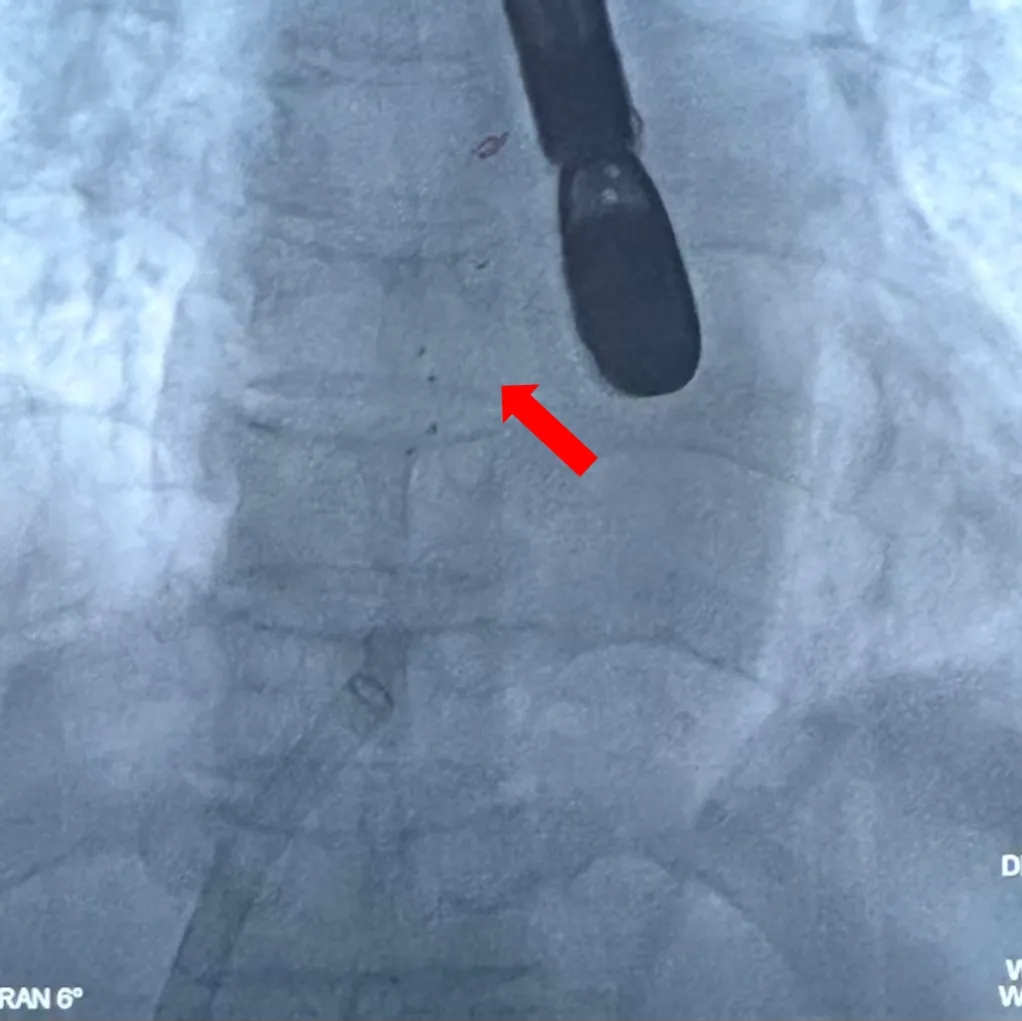

术中复测:术中食道超声下复测缺损大小,缺损大小为14.5mm,合并软缘11.7mm,其他边缘充足。

封堵策略:考虑到缺损的软缘范围较大,且房间隔总长足够,选择BDASD-Ⅰ30可降解房间隔缺损封堵器,配合I-16F可降解封堵器介入输送系统实施封堵。

术中复测

术中测量软缘长度

术中复测缺损大小

剑下双房心切面测量上腔静脉侧边缘